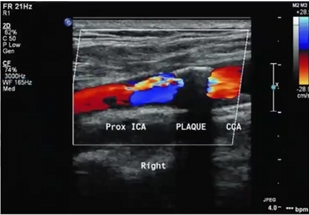

Patient presents to ultrasound department for preoperative work-up. Patient scheduled to have coronary artery bypass graft (CABG) in two days. Patient has HX of peripheral vascular disease, smoking, HTN and hyperlipidemia. You obtain this image. Consider following questions.

1. Is it possible to have plaque producing stenosis without symptoms?

2. What are the risk factors for atherosclerosis in this patient presentation?

3. Is this image diagnostic for hemodynamically significant stenosis? Why or why not.

Yes

Hx of peripheral vascular disease, smoking, HTN, hyperlipidemia. (Also has CAD because they are here for pre op for CABG)

No because power doppler only shows presence of flow and no velocity information